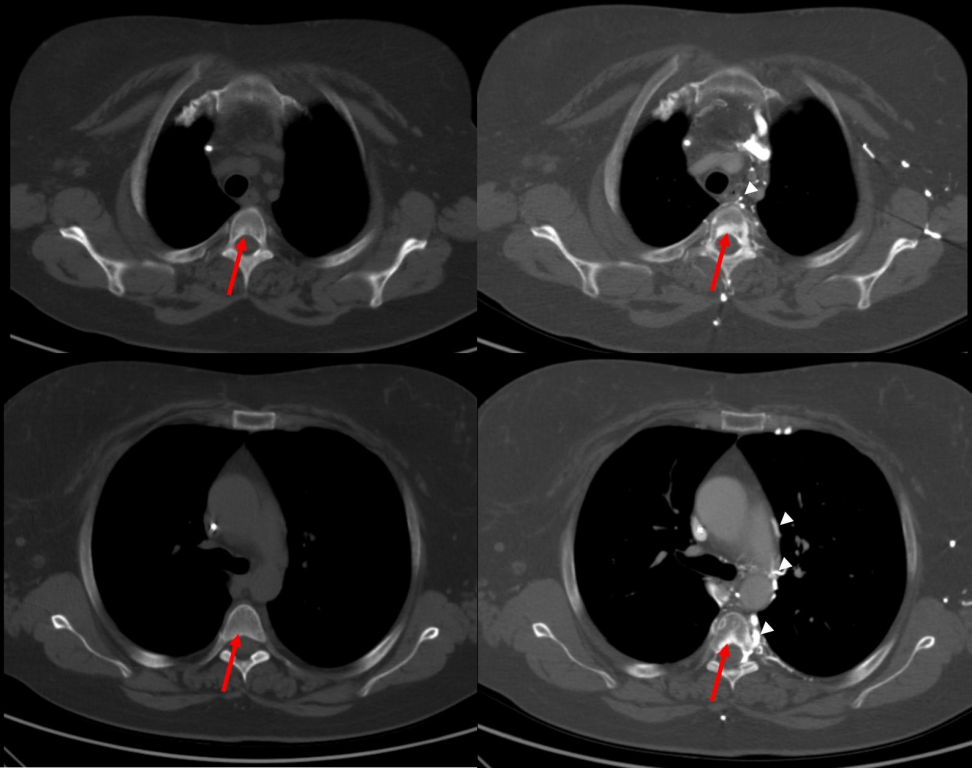

胸部增强CT扫描显示:双侧无名静脉和上腔静脉起始段(位于奇静脉汇合点上方)存在阻塞,但未观察到明显局部淋巴结肿大或任何表面肿块的证据。

我们分析认为,这些阻塞现象可能与多次化疗过程中导管插管操作引发的纤维化反应有关。

正如预期,我们还观察到由于静脉阻塞而形成的丰富侧支循环,这些循环涉及常见的和较少见的血管通路,包括奇静脉-半奇静脉系统、内乳动脉-腹壁下血管、椎基静脉丛以及心包膈静脉(后者引流至下腔静脉)。

同时,我们还注意到以第一胸椎椎基静脉孔为中心的三角形强化区域,在相同层面的非增强CT扫描中并未显示出任何显著的异常密度(见下图)。